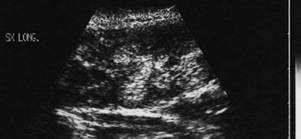

Lob stang, proiectie trasversala si longitudinala

Barbat de 55 ani. Formatiune nodulara voluminoasa ce ocupa 2/3 din lobul stang, hipoecogena, neomogenea, de 20 x 23 x 44mm(10 cc). Citoaspirata ecoghidata: carcinom midolar. Confirmat histologic.

Scintigrafia si CT aceluiasi pacient, metastaza laterocervicala stg ce impinge traheea spre dr.